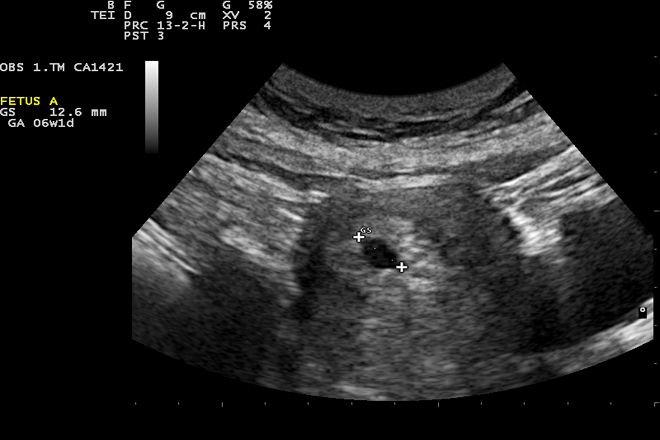

En este trabajo se reporta el caso de una paciente de 35 años con embarazo ectópico con implantación en la cicatriz de una cesárea previa. La paciente presentaba antecedentes de 4 gestas previas, dos de los cuales fueron cesáreas. Ingresa al servicio de Urgencias por sangrado transvaginal abundante de 15 días de evolución. Por fecha de última menstruación se determinó gesta de 11.3 semanas La paciente a su ingreso se encontraba hemodinámicamente inestable, sin signos de irritación peritoneal, presentaba cuello uterino violáceo, edematizado, hipervascularizado, fondos de saco libres y al tacto vaginal sin alteraciones. Al ultrasonido abdominal se constató la existencia de un embarazo de 11.5 semanas de gestación, con implantación corporal baja, embrión único con frecuencia cardíaca fetal de 157 latidos por minuto. Los ultrasonidos transvaginal y translabial reportaron que la placenta estaba en la pared anterior, previa total con pérdida de interface entre el miometrio y la placenta, el Doppler sugirió acretismo placentario.

Este tipo de embarazo se diagnostica entre las semanas 5.0 y 12.4 de la gestación (ẋ 7.5 ± 2.5 semanas) con un periodo de seis meses a doce años entre la última cesárea y el embarazo ectópico previo.

Se menciona en la publicación un trabajo en el que se propone una lista de criterios ultrasonográficos para establecer el diagnóstico: a) aparición de tejido trofoblástico entre la vejiga y la pared anterior del útero; b) saco gestacional, sin partes fetales visibles; c) en un corte sagital del útero siguiendo el saco gestacional, con pérdida de la continuidad en la pared anterior del útero. En los casos de embarazo temprano, el ultrasonido Doppler, Doppler color o en tercera dimensión pueden ser de gran ayuda para observar el patrón de flujo (pico de velocidad mayor de 20 cm por segundo), índice de resistencia y de pulsatilidad (IP <1) de la vasculatura peritrofoblástica y con esto excluir o confirmar el diagnóstico. Se reporta que su sensibilidad es de 84.6% con IC95% (0.763-0.905).